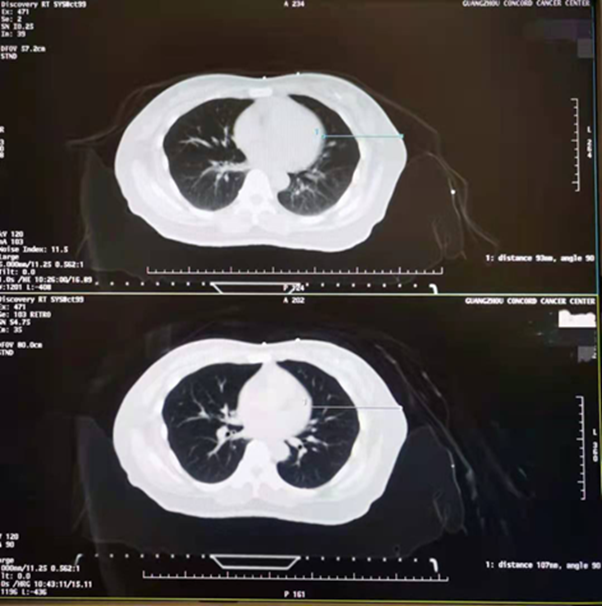

▲ 自由呼吸(上图)与 DIBH(下图)

两种状态下乳腺与心脏的距离对比